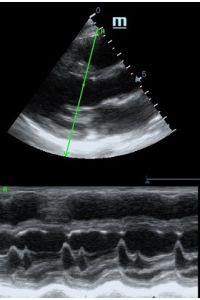

Но как же провести стандартные измерения в М-режиме, если мы его не использовали? На помощь приходит функция Free Xros M – анатомический М-режим. Имея записанную в память прибора видео петлю, мы можем провести линию М-режима в любом месте, при этом корректируя изначально не оптимальный угол.

Оценка сокращения сегментов левого желудочка на глаз постепенно уходит в прошлое. Если в приборе нет функции радиального или лонгитудинального стрейна, на помощь опять может прийти Free Xros. Утолщение более 5 мм в систолу – нормальное сокращение, 2-5 мм гипокинез, истончение в систолу – дискинез.